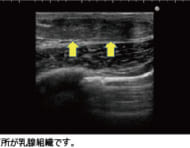

Yokohama Staff 女性化乳房と言われたら読んで欲しい~原因と治療法の解説~ 男性なのに、女性のように胸が膨らんでしまう状態を女性化乳房と言います。見た目だけでなくしこりや痛み、乳輪の色味が女性的に変化する(ピンク色に変化する)など様々な… 女性化乳房 2018-01-16 2018-01-16 Yokohama Staff

shida 女性化乳房の悩みは、胸の膨らみだけにあらず 女性化乳房と言えば、男性の胸が女性のように膨らんでしまう症候群です。この女性化乳房患者さんがよく訴えて来られる共通の症状は、胸の膨らみ以外にもいくつかあります。… 女性化乳房 2017-11-28 2017-11-28 shida

chiba 【検証】女性化乳房は筋トレやダイエットで改善できるのか? 男性なのに女性のように胸が膨らんでしまう、女性化乳房。「筋トレやダイエットをすれば症状を改善できるのでしょうか?」 という相談を時々いただくのですが、これまでの… 女性化乳房 2017-11-09 2017-11-09 chiba

higuchi 乳輪のふくらみが気になるという女性化乳房症例 男性の中には、人知れず胸の膨らみで悩んでおられる方が少なくありません。 当クリニックにも、たくさんの男性から胸の膨らみに関する相談が寄せられます。 その多くは「… 女性化乳房/胸部 2017-09-08 2017-09-08 higuchi

chiba 真性女性化乳房治療の実際を、医師目線で完全レポート 今回は女性化乳房のモニターゲストをご紹介します。 女性化乳房には大きく2種類、乳腺の発達が原因の真性女性化乳房と、脂肪の蓄積が原因の偽性女性化乳房がありますが、… 女性化乳房 2017-08-25 2017-08-25 chiba

kato 女性化乳房の治療法とよくある質問 夏本番を目前に控えた初夏の季節、多くの男性から寄せられる相談といえば「女性化乳房」についてです。胸に膨らみがあってプールや海に出かけられない、Tシャツ姿になれな… 女性化乳房 2017-08-18 2017-08-18 kato